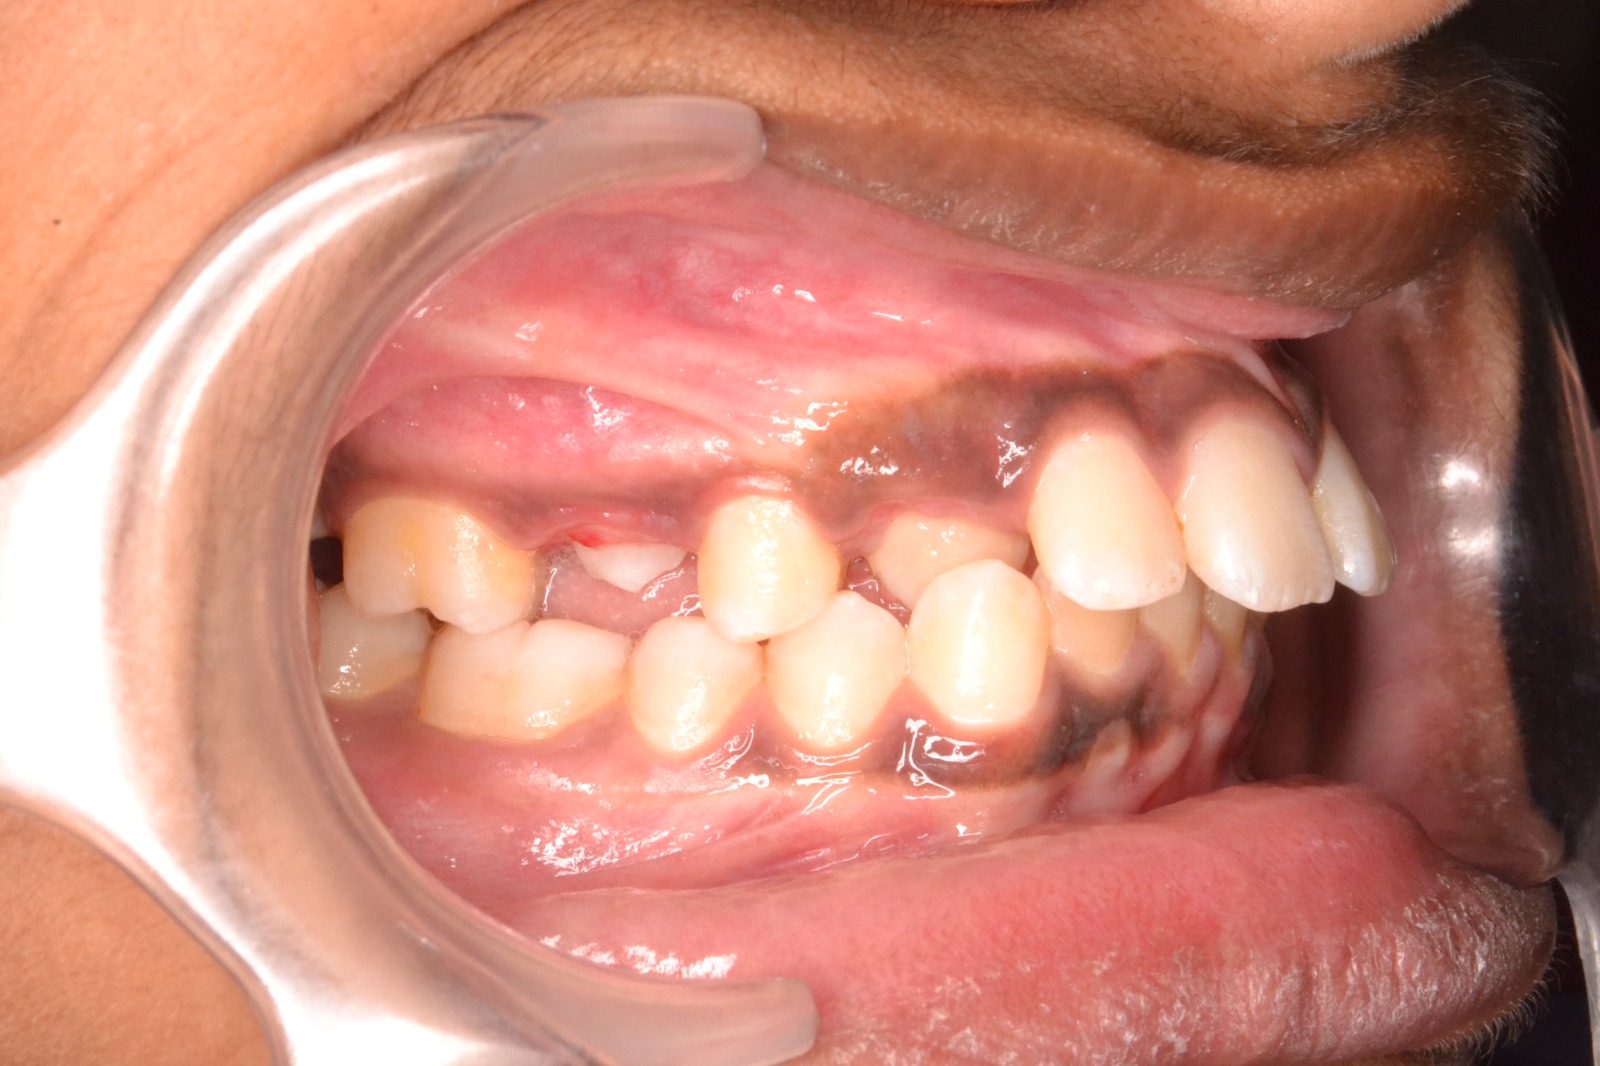

Sairam dental care located in Dharmapuri, with Leading Dentist In Oddapatti, is the Dental Hospital with exclusive root canal, Braces & Invisalign center. Led by renowned Drs Raghuraaman ( Periodontist) and Nivetha Raghuraaman ( Orthodontist) Sairam dental care offers gum treatment with expertise in laser, root canal treatment and digital smile correction with advanced technology aim to focus on aesthetics, comfort and precision. The clinic also specializes in Invisalign treatment, digital smile makeover, laser gum care, dental implants, root canal therapy, extractions and full-mouth rehabilitation blending compassionate care and clinical excellence.